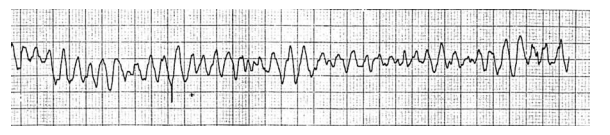

Durante o atendimento de vítima em parada cardiorrespiratória, foi realizada, no segundo ciclo, uma desfibrilação com 200 J e administrado 1 mg de adrenalina. Após manutenção das manobras de ressuscitação cardiorrespiratória e nova análise do ritmo (registro a seguir), foi realizada uma nova desfibrilação.

Qual o próximo medicamento que deverá ser administrado?